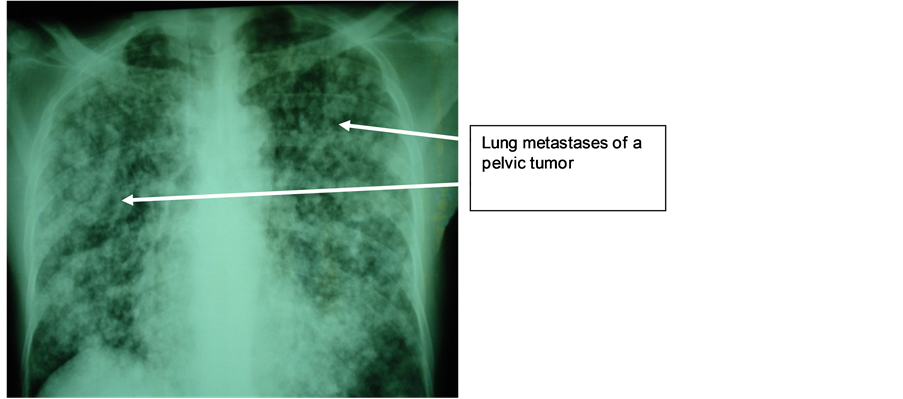

Mr. M.N., 47 years old, with a long history of left lower back pain relieved by usual analgesics, was hospitalized in emergency for lumbago, hematuria, fever at 39˚C and altered general condition. Physical examination revealed hematic urines and a right lumbar fossa sensitivity. Biological and bacteriological laboratory exams revealed a hyperleukocytosis and a Klebsiellapneumoniae infection in urine cultures. The ultrasound showed that the right kidney was enlarged, with highly dilated cavities and heterogeneous content. The CT scan showed an enlarged right kidney, cavities with heterogeneous content (pyonephrosis) and a significant dilatation of the left pyelocaliceal (Figure 4). Right pyonephrosis was diagnosed and a left ureteropelvic junction syndrome was also suggested. Treatment included a left nephrostomy and a right nephrectomy. The macroscopic aspect was in concordance with morphological data, revealing a pyonephrotic kidney and a right pyelocaliceal tumor. The postoperative course was marked by a parietal suppuration on the third day. Histological analysis of the resected specimen indicated that it was a low-grade papillary carcinoma of the urinary tract (PT3G1 stage). Postoperative follow-up showed a recurrence two months later on the remaining ureteral stump by ultrasound, as well as celiac lymph nodes, and spleen and liver metastases. Chest X-ray also revealed lung metastases (Figure 5). The patient died two months after surgery.

Figure 5. Lymphangitiscarcinomatosis (TVES (tumeursdes voies excrétrices supérieures) metastases).